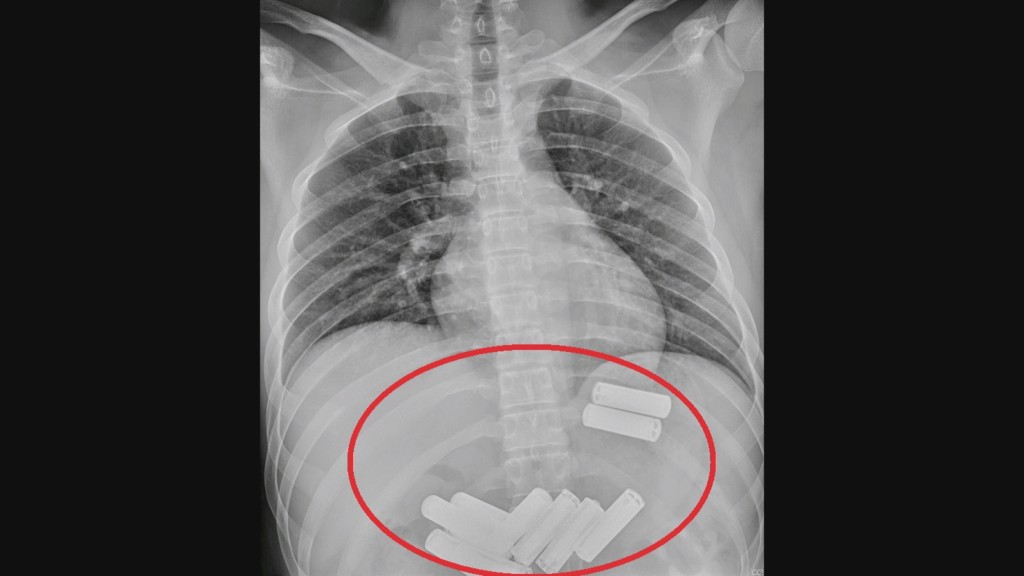

Mladić u Kini progutao je 11 baterija pa je podvrgnut endoskopskoj metodi vađenja baterija iz želuca.

Ljekari u kineskoj regiji Miaoli su endoskopskom metodom izvadili 11 baterija koje je 23-godišnji Lee progutao iz znatiželje.

List “Taipei Times“ javlja da je prijatelj doveo Leeja u bolnicu Da Chien i da su ljekari tek rendgenskim snimkom otkrili da u želucu ima baterije.

Baterije su izvađene nakon jednosatne endoskopije.